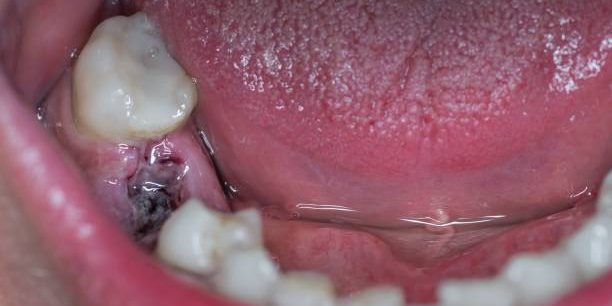

Several case reports in the literature describe OSCC initially misdiagnosed as peri-implantitis. This is a clinically important finding. If a peri-implant lesion does not respond to standard periodontal treatment, presents with unusual features such as rapid onset, tissue induration, altered sensation (paraesthesia or anaesthesia), or ulceration, a soft tissue biopsy should be performed promptly.

Early-stage OSCC is highly treatable. Delayed diagnosis because of a presumed inflammatory aetiology carries significant prognostic consequences.

- A peri-implant lesion or swelling that does not resolve after 6–8 weeks of appropriate treatment

- Ulceration or irregular tissue growth around an implant site

- Unexplained numbness, tingling, or altered sensation (paraesthesia) in the jaw, lip, or tongue

- Rapid bone loss or implant mobility without clear cause

- Persistent pain unrelated to normal healing timelines

If you notice any of these symptoms, contact your dental practitioner immediately. They may recommend a soft tissue biopsy and/or referral to an oral and maxillofacial surgeon for specialist review.